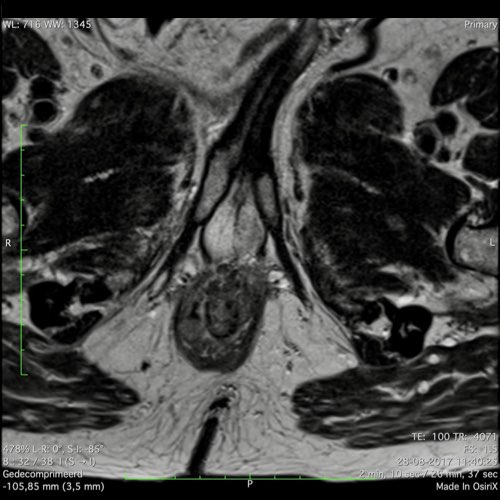

Hình ảnh

Các hình ảnh được cung cấp cho thấy ung thư biểu mô tế bào nhẫn với tình trạng dày lan tỏa thành trực tràng, hình ảnh bia bắn điển hình, và sự xâm lấn mỡ mạc treo trực tràng.